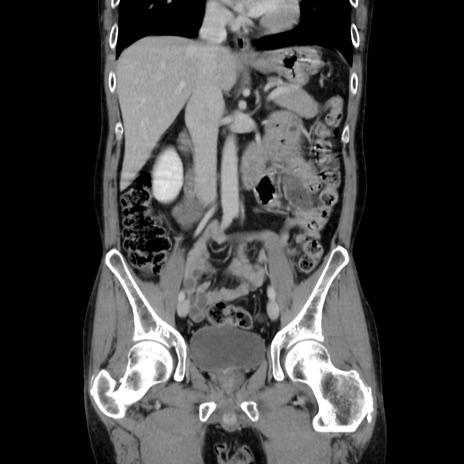

横断像

【症例】40歳代 男性

【主訴】腹痛

【現病歴】4時間ほど前に電車に乗車中に臍部上より腹痛出現。徐々に増悪し起立困難となり、救急外来受診。生ものは数日食べていない。今朝お雑煮を食べた。

【身体所見】BT 36.8℃、BP 117/84mmHg、HR 91/min、SpO2 97%、苦悶様、腹部:臍上部広範囲圧痛あり、反跳痛±

【データ】WBC 8100、CRP 0.03